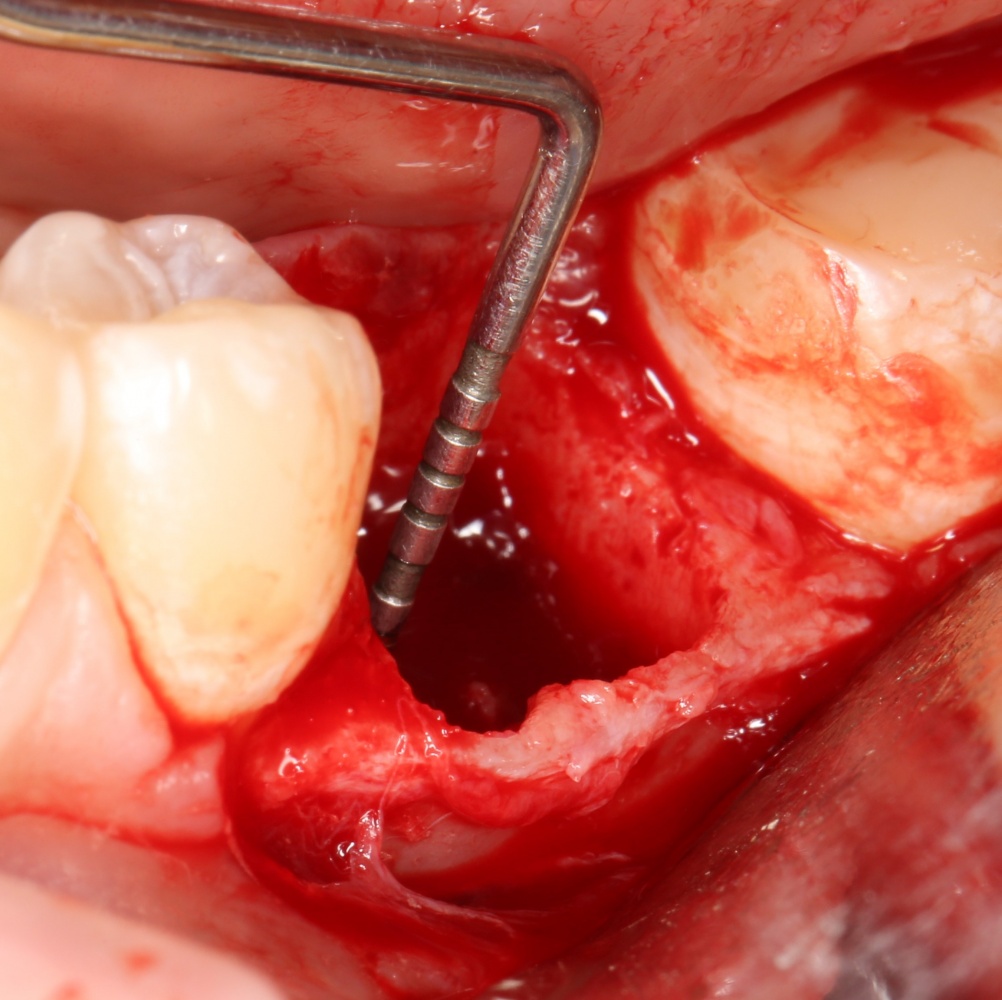

Рекомендации по установке имплантов. Для всех. Часть II.